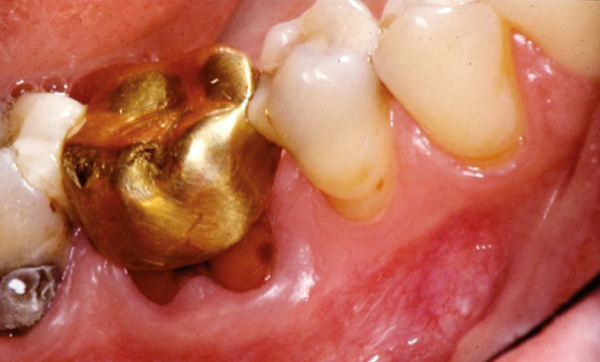

L’examen clinique montre que cette dent, couronnée, présente des joints médiocres (dus à l’ancienneté de la prothèse), une poche de plus de 10 mm en mésial et une douleur à la percussion verticale.

L’examen radiographique met en évidence un traitement endodontique incorrect, une lésion périapicale et une poche parodontale infra-osseuse au niveau de la racine mésiale (fig. 1 et 2).